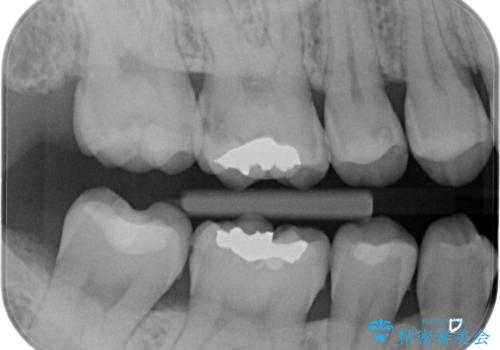

奥歯の虫歯の治療

- 奥歯が虫歯になっていたため治療しました。

手前側の歯は前から見えるため、セラミックの詰め物で治療しました。

奥は高さを取るのが難しかったため薄く作れる金属(ゴールド)で治療しています。

- 合計 26.4万円(内訳:右上7 PGAクラウン 11万円(旧料金)、右上6PGAインレー 7.7万円(旧料金)、右上5 emaxインレー 7.7万円)費用は治療当時の料金となります

今後の虫歯予防に、治療と合わせて歯磨き指導も行っているため、清掃状態も大きく改善しています。